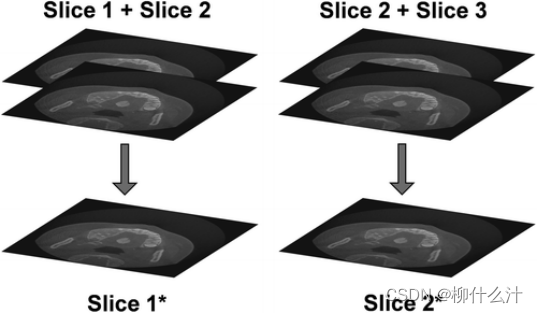

增加切片厚度意味着创建了一个新的图像(例如:切片1*),其中每个切片是原图像的多个(在本例中是两个)切片的平均值。切片的总数不会改变。